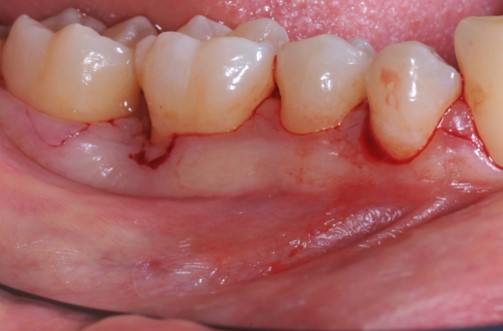

Radiographic view before periodontal regenerative therapy with Straumann® Emdogain®. A deep intrabony defect appeared mesially and distally on the left mandibular first premolar. Pre-surgical probing measured 8 mm. The defect morphology presented as well-contained.